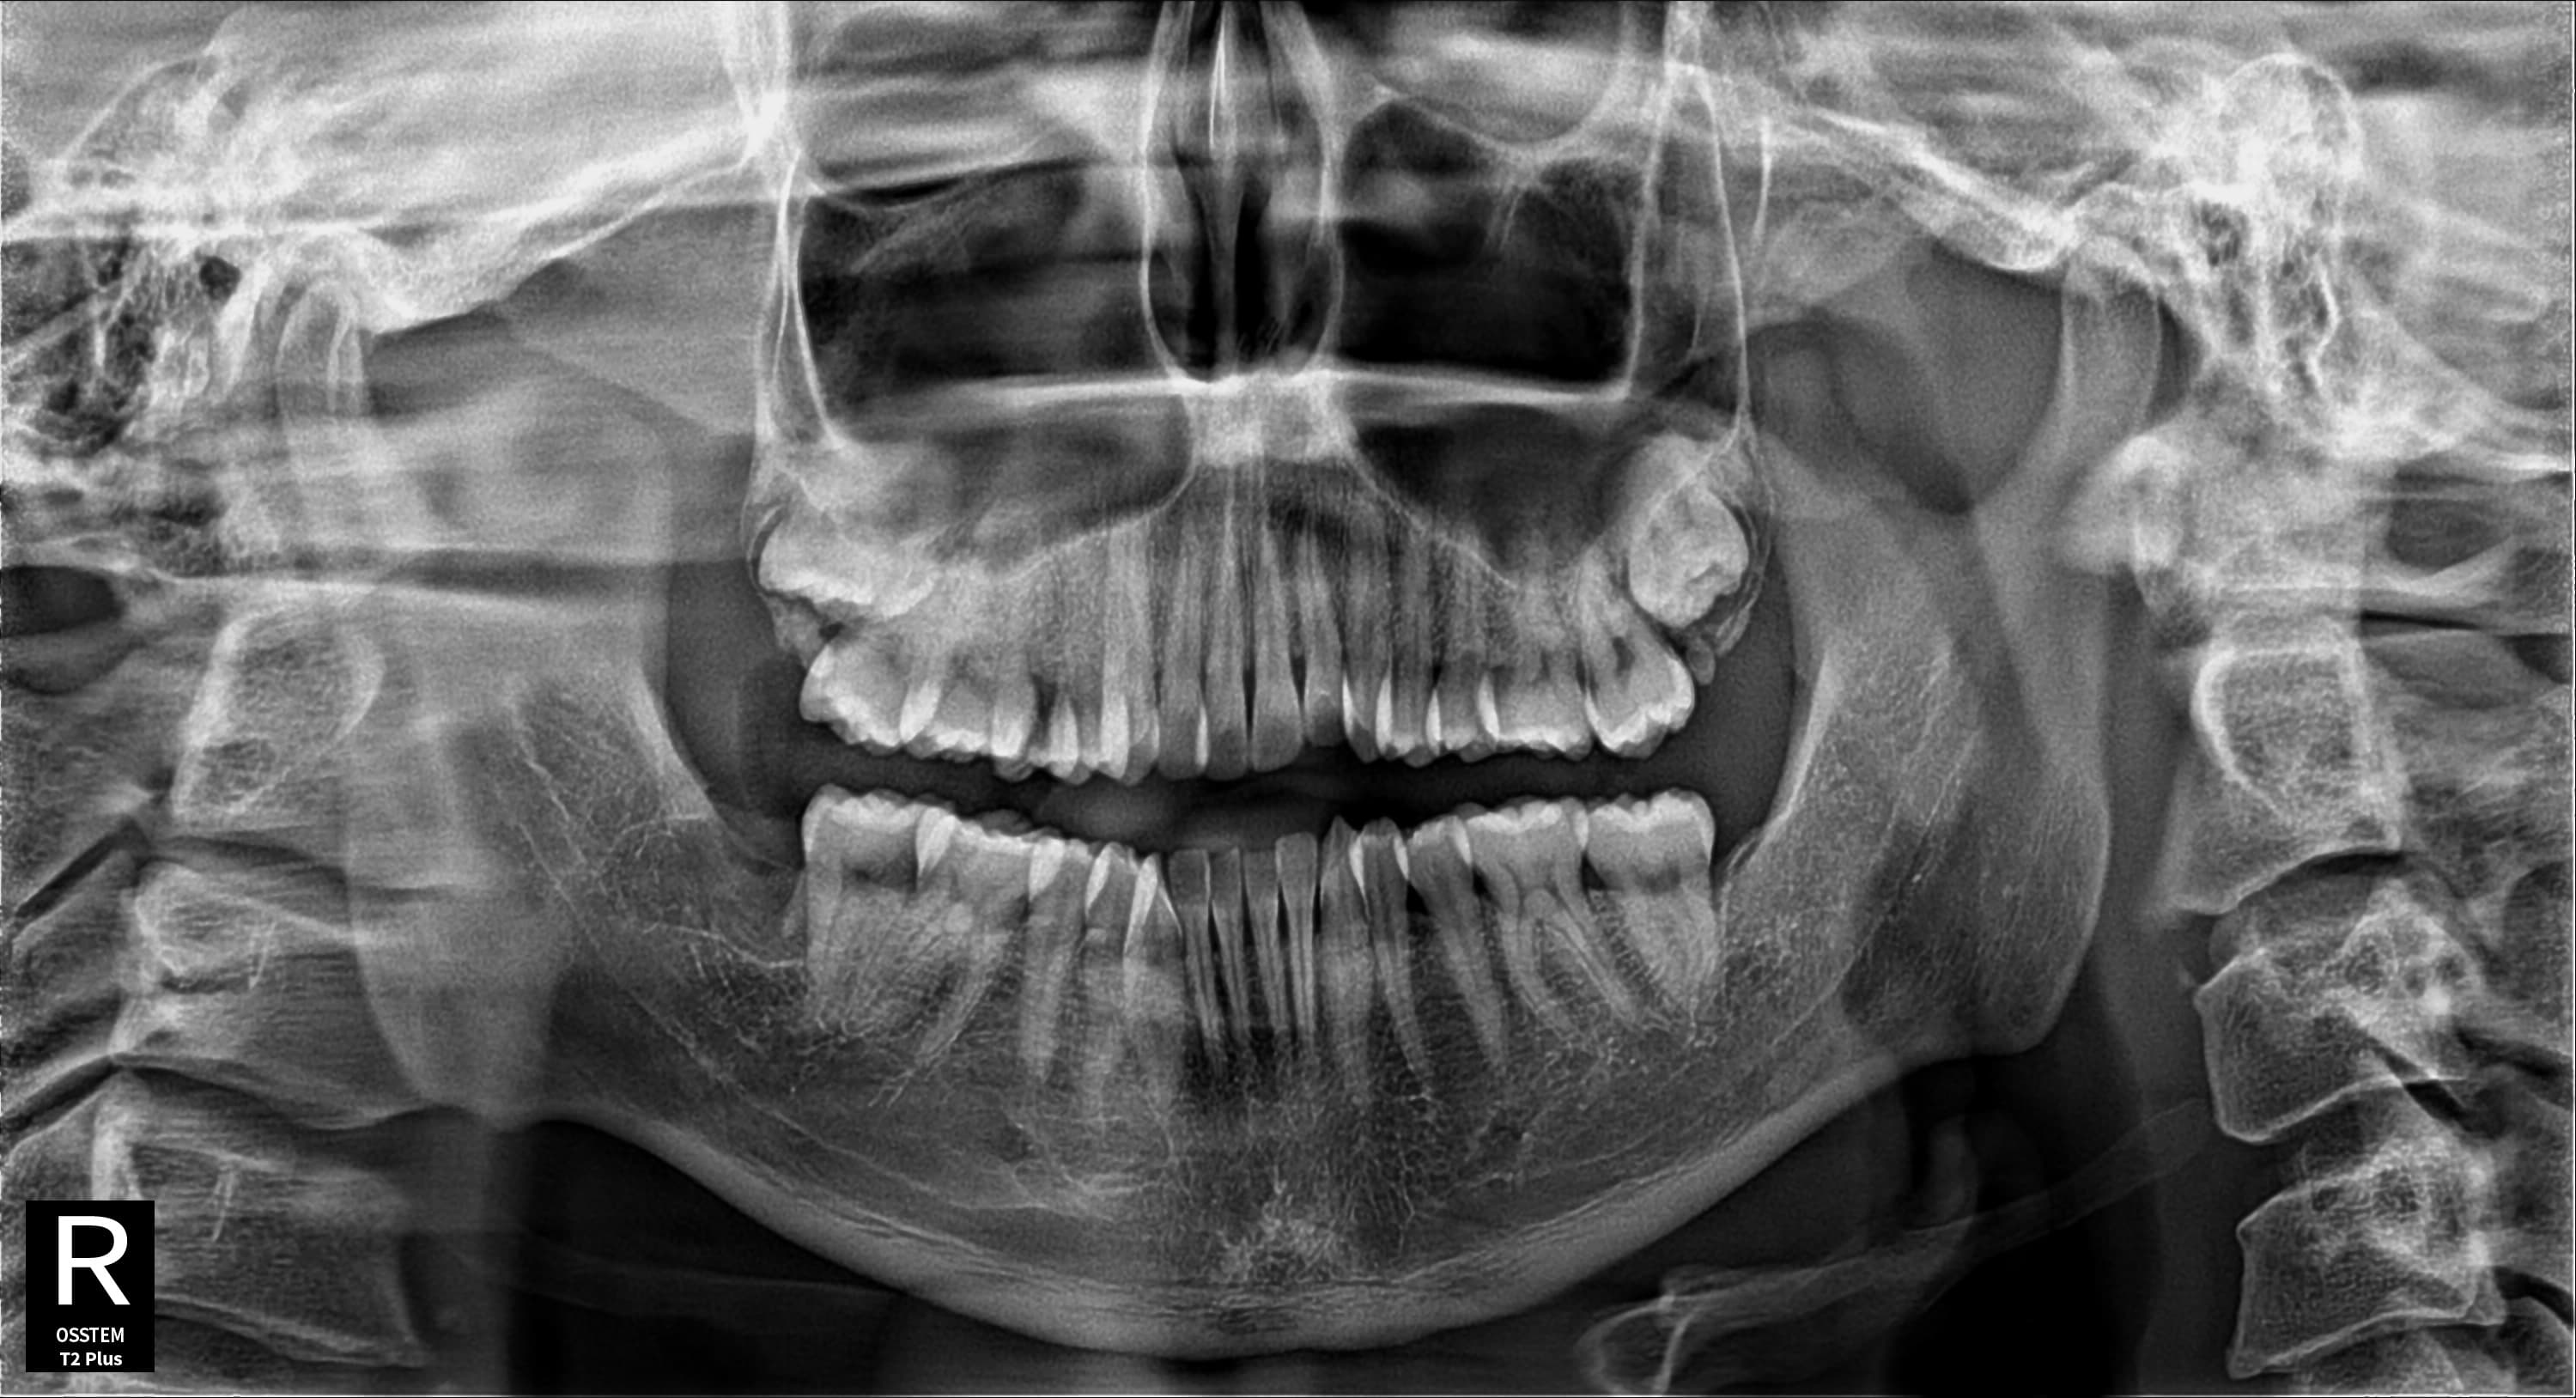

왼쪽 아래 사랑니 발치

왼쪽 아래 매복 사랑니 안전 발치

Before

After

매복된 왼쪽 아래 사랑니를 안전하게 발치 완료